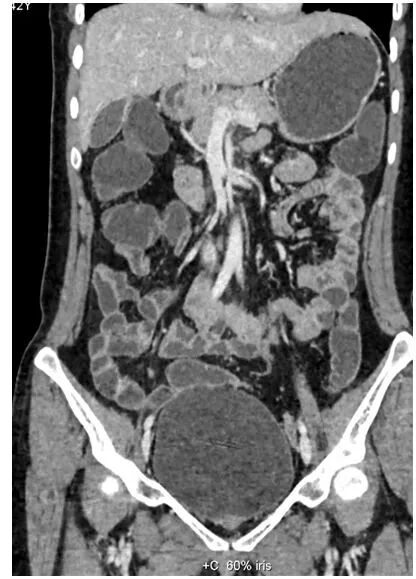

完成2米范围全身动脉扫描仅需3秒,即可得到清晰图像。

全新0兆球管可持续行大范围扫描,轻松应对双下肢动脉CTA检查。